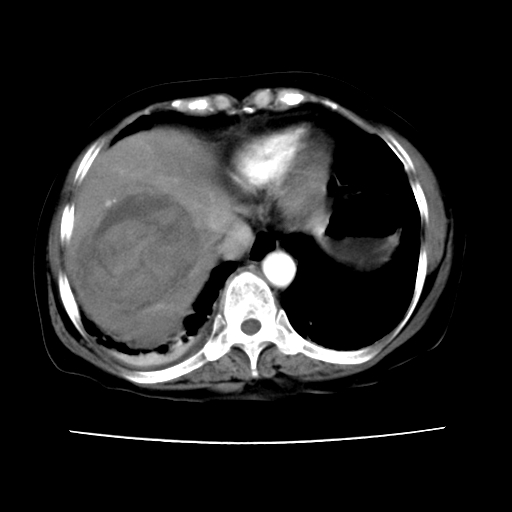

标题: CT16642:男62岁,突发性上腹部疼痛来诊。请讨论!

2008-6-10ct平扫

ct增强

6月片:肝血管瘤并破裂出血?肝左外叶囊肿

考虑肝腺瘤出血可能,肝血管瘤增强表现不是很典型,放在第二。

考虑为肝血管瘤破裂出血并肝包膜下血肿;右侧少量胸腔积液。

符合肝癌破裂出血并包膜下血肿。

6月份ct片显示肝内巨大混杂密度团块,伴包膜下积液(内含液液平面),增强多无明显强化。只能考虑肝占位病变,并肝内、血膜下血肿。肝ca并出血多见,而肝血管瘤并破裂出血少见。